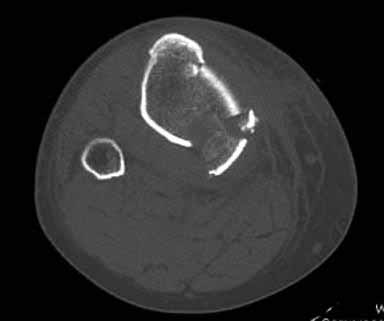

Здравствуйте уважаемые коллеги!Сегодня обратился больной 35л. Травму получил 3 мес.назад, упал в яму, лечился в отдаленном районе гипсовой повязкой, 1 месяц назад гипс сняли , и больной начал ходить с нагрузкой, постепенно появилась деформация коленного сустава, неустойчивость и боли. Локально: деформация коленного сустава, голень смещена кзади- типа подвывиха, разгибание 170гр. Сгибание 150гр.симптомов повреждение коллатеральных и крестообразных связок определить не удается из-за боли и контрактуры. Первичных снимков пока нет, обещали принести, имеется снимки через 2 месяца после травмы без гипса, недельной давности снимки в прямой проекции и К Т. Похоже, что импрессия переднемедиальной части внутреннего мыщелка б/берцовой кости, отрыв межмыщелкового возвышения.

На снимке типичный перелом медиального тибиал плато с передним смещением (подвывих) по Schatzker IV. Консервативное лечение без медиальной опоры не может удержать деформирующие силы, и из-за вторичного смещения мыщелка конечность смещается в варус. Кроме передних смещений еще встречаются сложные фронтальные варианты переломов, и тогда голень подвывихивается кпереди.

А в данном случае мыщелок сросся со смещением кпереди и ротирован. За счет интактной наружной колонны опороспособность конечности сохранена, но остается варус и экстензия конечности. Для предоперационного расчета необходимо сделать на всю длину конечности рентгенограмму, а в остром периоде КТ и 3-мерный снимок помогут лучше ориентироваться в характере перелома.